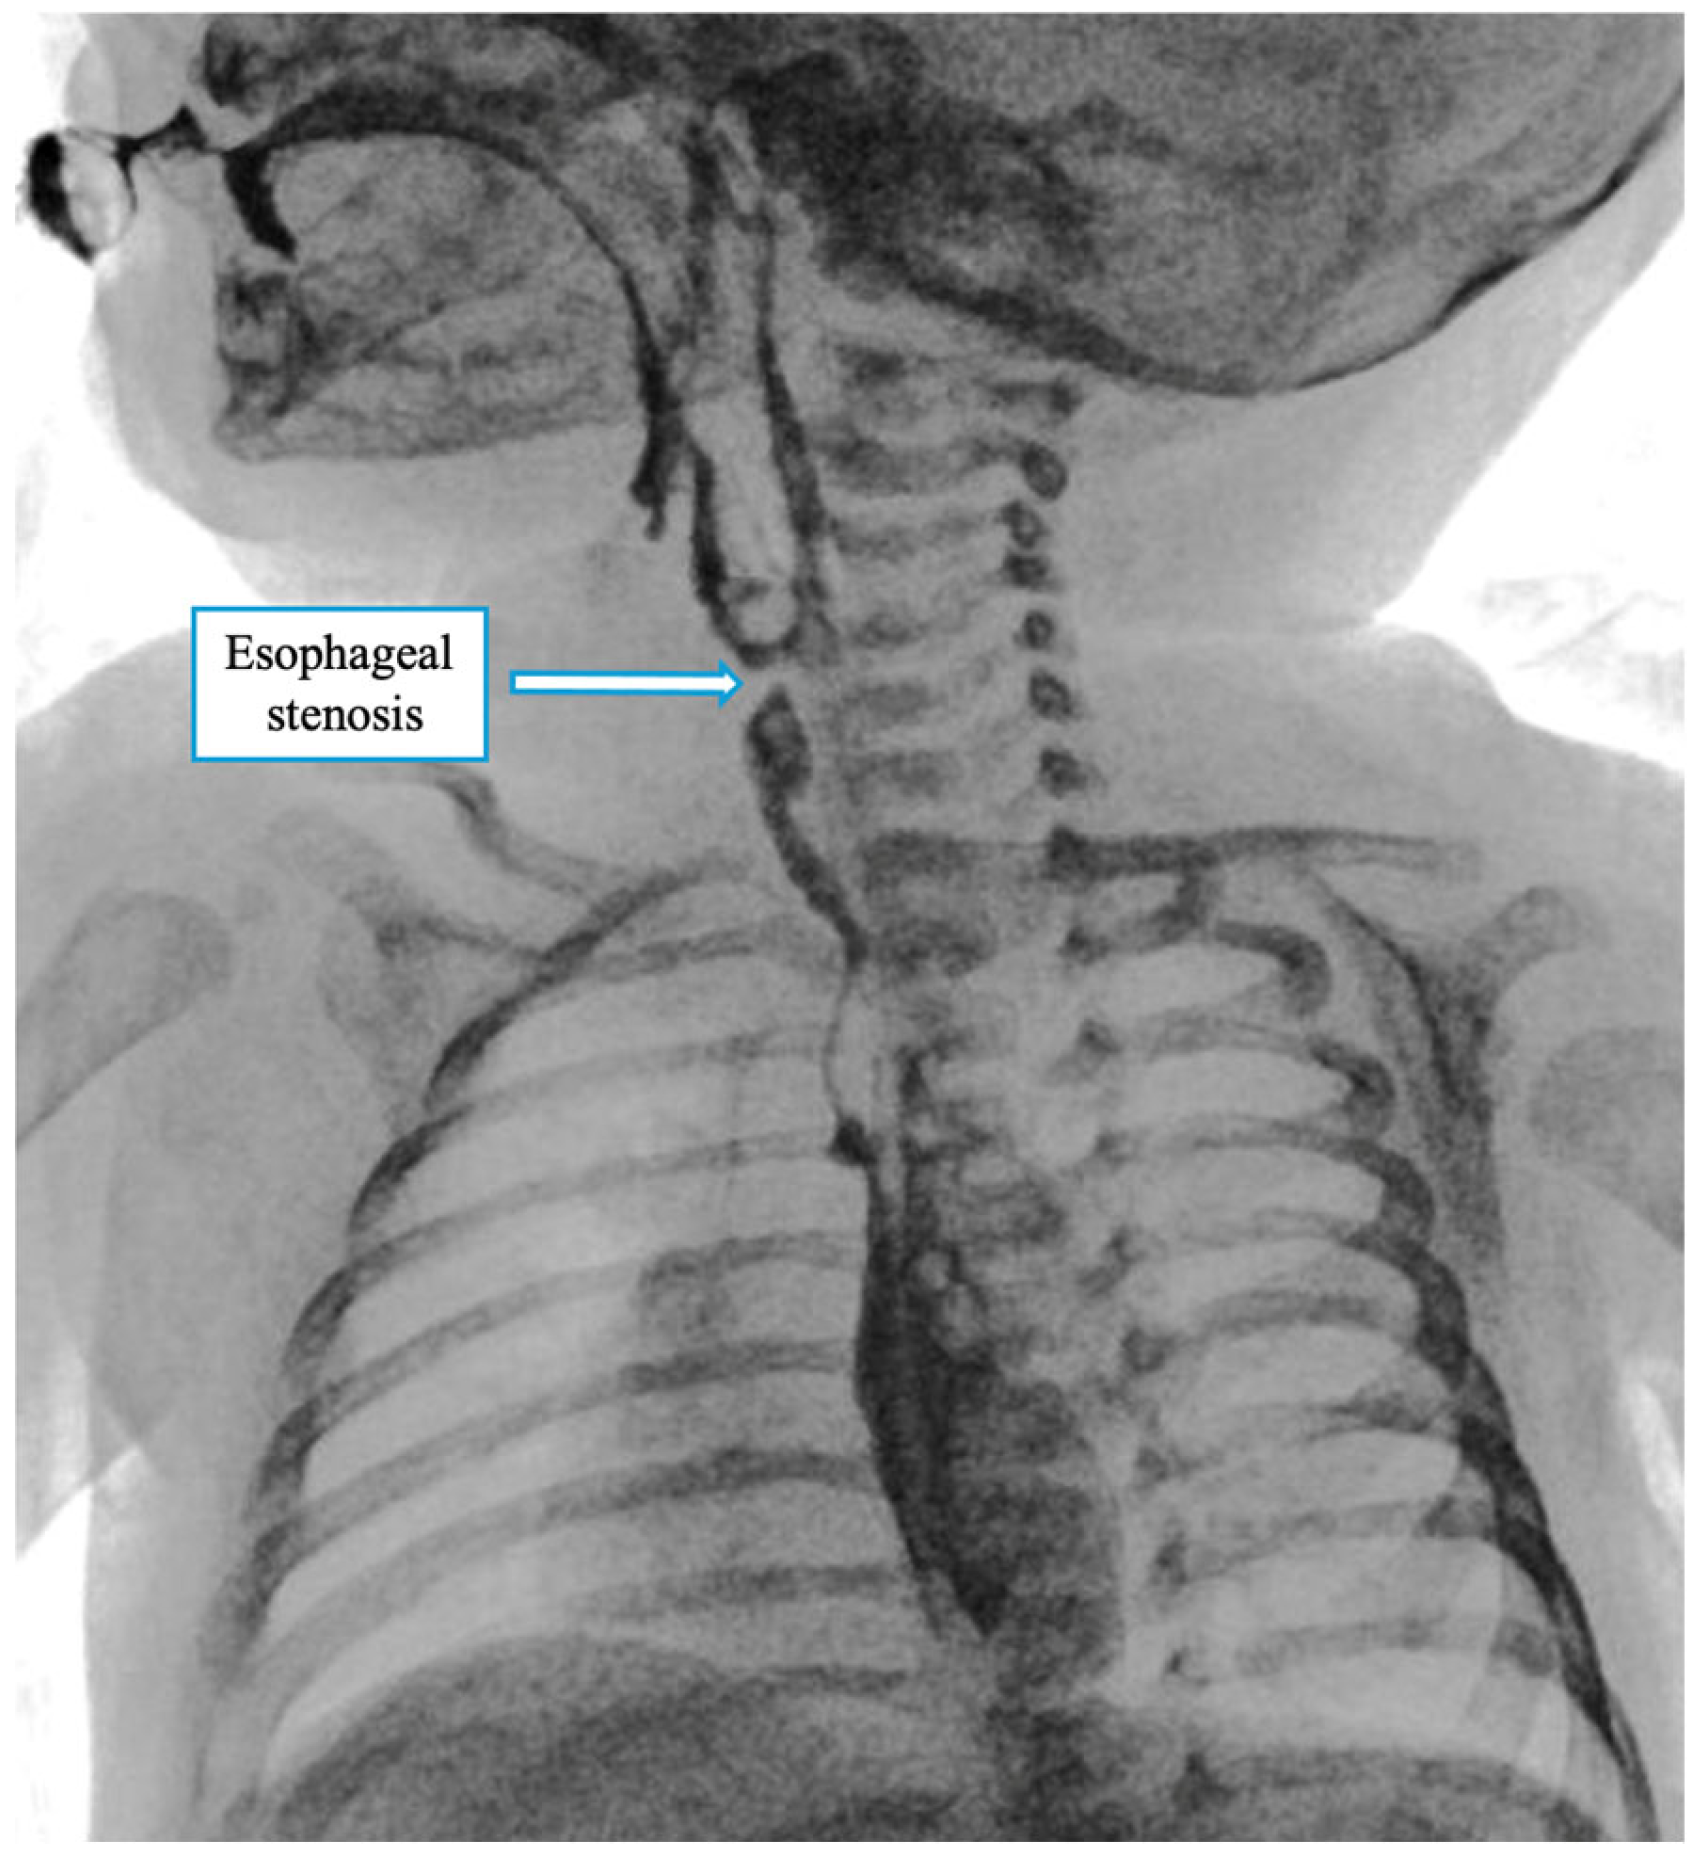

A contrast X-ray performed on postoperative day VII showed stenosis at the anastomotic site (Figure 5). The patient underwent serial esophageal dilations (10 session) up to a caliber of 10 mm, and until clinical stability and good tolerability of oral feeding were achieved. During this period, oral intake improved gradually, and by the end of the third month, the patient had achieved stable, full oral feeding. At the latest follow-up at 6 months of age, the child was tolerating an age-appropriate oral diet without feeding-related difficulties, and growth parameters were within the normal range.

Figure 5. Postoperative contrast study on day 7 showing a mild narrowing at the anastomotic site, consistent with a benign stricture. No contrast leakage was observed.